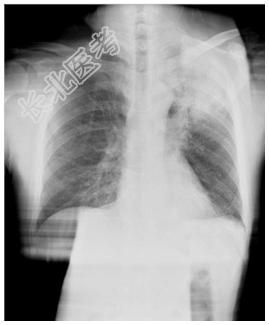

- [材料题] 女性,55岁,10余天前出现午后潮热(约38.5℃),无伴盗汗,有咳,痰少、带血丝,发病以来体重减轻5Kg,大小便正常,否认肺结核等病史。一般情况:无特殊。体查:左胸呼吸运动减弱,左侧语颤增强,左上肺叩诊浊音,并闻及干性啰音,语音传导增强。实验室检查:血常规及肿瘤五项、AFP、CEA均在正常范围。痰涂片未见真菌,未见抗酸杆菌,发现少量酵母样菌。

- 简答题1、患者的诊断及依据是什么?

- 简答题2、鉴别诊断有哪些?